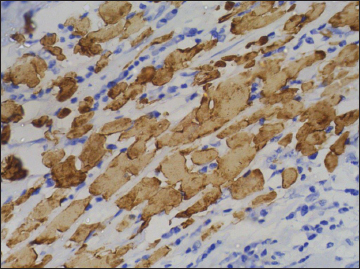

| Figure 5 Immunohistochemistry on esophageal specimen showing strong positivity for CK5/6